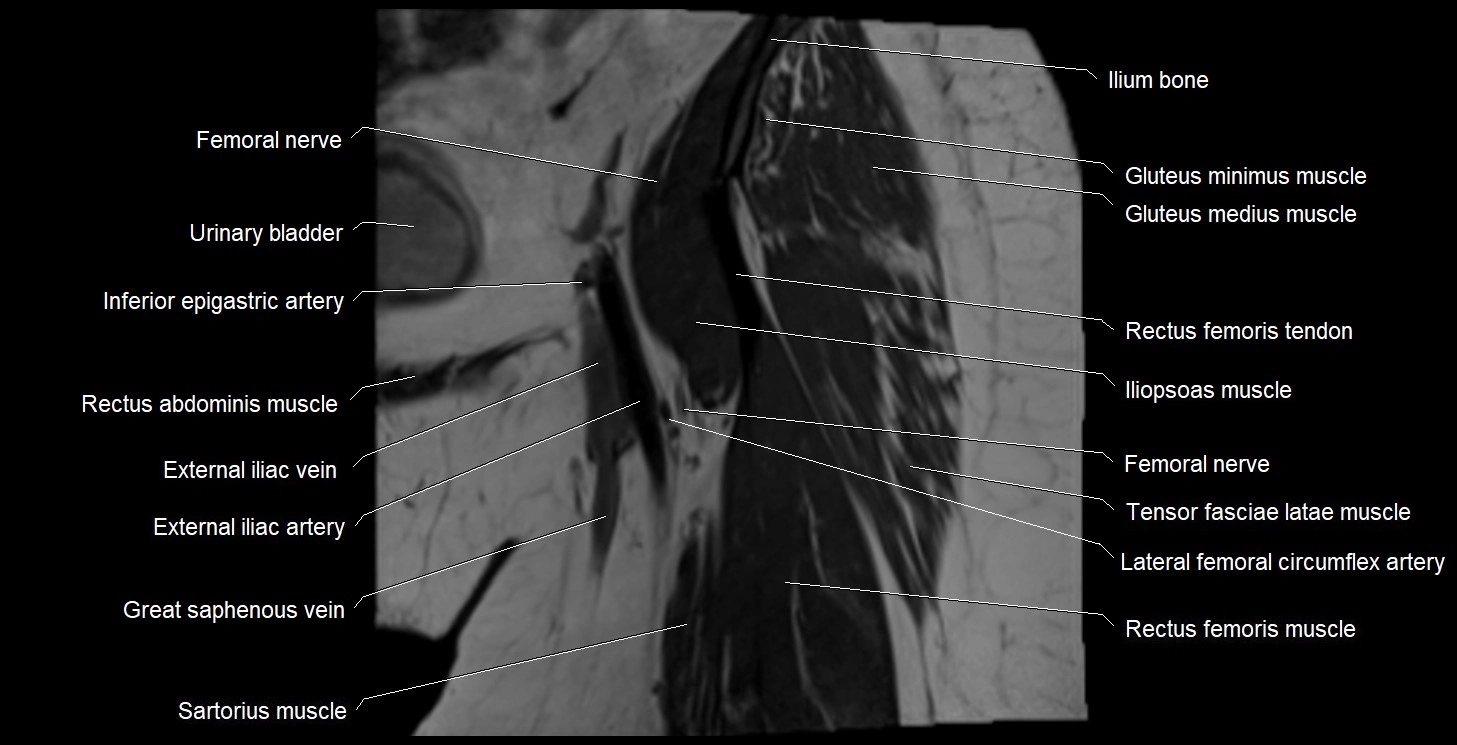

- External iliac artery

- External iliac vein

- Femoral nerve

- Gluteus medius muscle

- Gluteus minimus muscle

- Iliopsoas muscle

- Iliotibial tract

- Ilium bone

- Inferior epigastric artery

- Lateral circumflex femoral artery

- Rectus femoris muscle

- Rectus femoris tendon (Proximal tendon of rectus femoris)

- Tensor fasciae latae muscle

- Urinary bladder